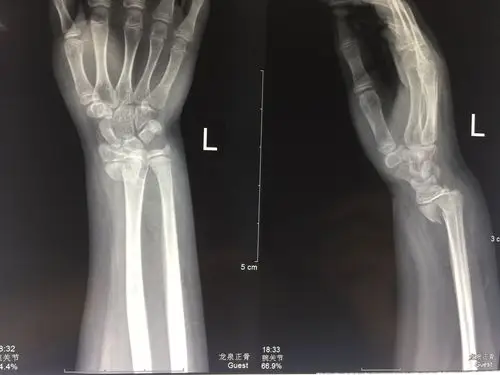

骺损伤,手法复位,完美愈 (原创)_桡骨